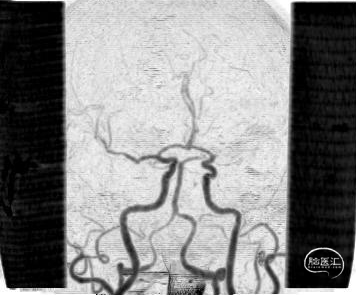

➢ 脑血管造影

➢ 手术指征

CTP提示左侧大脑中动脉供血区存在大片低灌注区。

经Stiff导丝更换6F金属长鞘,泥鳅导丝引导中间导管至左侧C2段;0.014inch微导丝导引微导管越过左侧大脑中动脉M1段闭塞病变段。

微导管造影提示位于血管真腔。

微导丝交换,分别以通桥白驹®颅内球囊扩张导管 1.25*8、1.5*10mm球囊扩张,复查造影血管狭窄程度较前好转。

经微导丝交换支架微导管,沿微导管送入4*39mm自膨支架至左侧大脑中动脉M1段闭塞病变处,支架成功打开,贴壁良好,支架内血流通畅。

➢ 术后造影